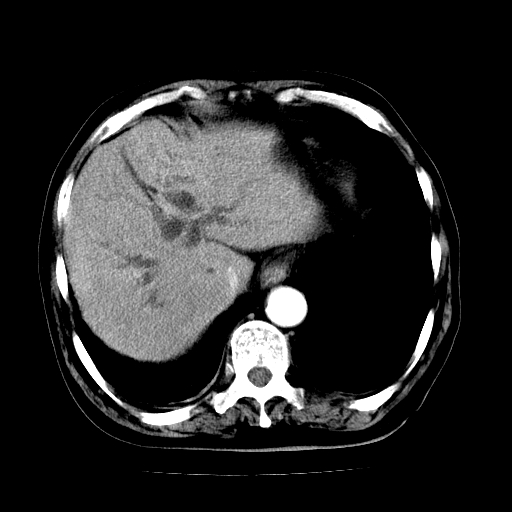

男,71岁,皮肤黄染四天。

肝内外胆管及胆总管上段扩张,考虑为梗阻所致,建议mrcp检查。

肝内胆管,胆囊,肝总管级部分胆总扩大张

胰腺上端胆总管内见软组织影,强化不明显,结合临床,还是考虑低位梗阻性黄疸,胆总管癌可能性大